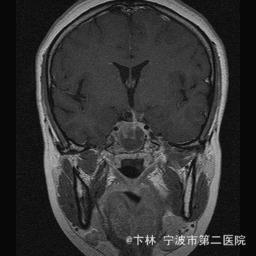

40岁女性,因“双眼视力下降三月余伴停经1个月余”入院。 患者三月前无明显诱因下出现双眼视力下降,视物模糊,尤以左眼为甚,只能近距离看到手动,无头痛、头晕,无恶心、呕吐,无视物旋转,无行走困难等不适,患者曾在某眼科医院就诊治疗,考虑为双眼视神经炎,予以营养,补液对症等治疗(具体不详),情况不见好转,近一月来患者月经停止,来我院神经外科门诊,予以查头颅CT,头颅MRI,提示“垂体大腺瘤”,为求进一步治疗收住入院

予以完善血,尿,粪常规检查,及凝血功能全套,输血功能全套及垂体功能全套,蝶鞍冠状CT等术前检查措施,行经蝶入路垂体瘤切除术。术后予以对症,补液,调节血电解质等治疗,患者视力明显改善,复查头颅MRI提示肿瘤基本全切,一周后患者出院。

此病人颅内垂体瘤体积较大,突破鞍隔压迫视交叉,故患者视力视野障碍为首发症状,该肿瘤主体有大部分向蝶窦腔生长,因此采用经蝶手术入路,肿瘤切除满意,术后患者视力视野恢复满意,。